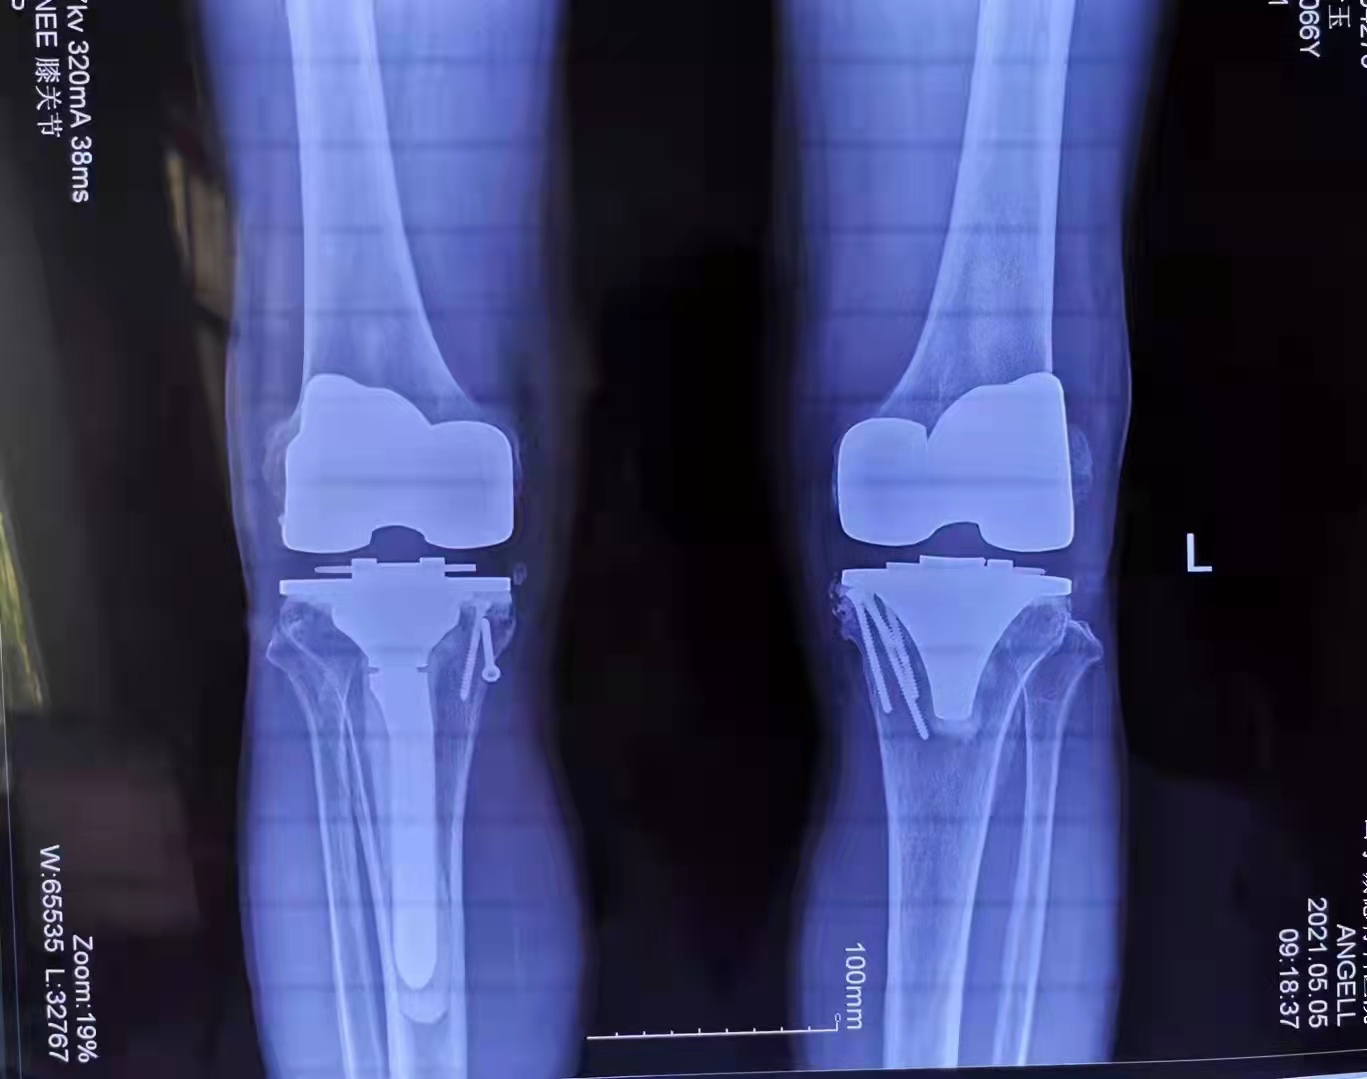

馬先生今年64歲,家住山亭區(qū)。換患雙膝關(guān)節(jié)骨性關(guān)節(jié)炎,造成下肢嚴(yán)重畸形,行走困難,疼痛難忍。在13歲時(shí)受傷骨折,沒有治療導(dǎo)致關(guān)節(jié)畸形、骨缺損。多年來傷病的困擾讓他痛不欲生。生活在困惑的黑暗中。

他來到了山亭誠德骨科醫(yī)院醫(yī)治,多年的頑疾。讓馬先生本沒抱有任何希望,然而,誠德骨科醫(yī)院的李俊鋒院長及團(tuán)隊(duì)給他帶來了希望,對(duì)這種復(fù)雜的病情進(jìn)行了精心的會(huì)診,制定了詳細(xì)而縝密的手術(shù)方案,予以分期進(jìn)行雙側(cè)膝關(guān)節(jié)置換手術(shù)。

手術(shù)恢復(fù)非常讓人滿意,馬先生已經(jīng)像正常人一樣參加工作,過上了幸福愉快的生活。